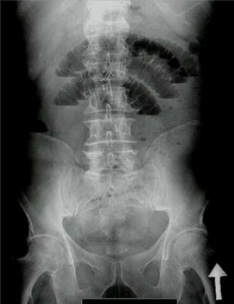

What are the top two causes of this?

1) Adhesions 2) Hernia. Note the dilated loops of bowel indicating small bowel obstruction.